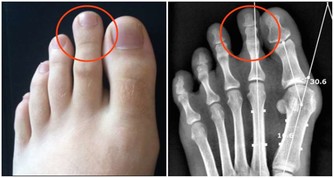

在中醫理論中,造成水腫的原因很多,除了器質性病變(例如腎臟病、心臟病等)之外,肺、脾、腎等3個臟腑功能失調,都容易引發水腫,治療上需辯證論治,視個人體質和症狀表現再對症下藥,量身處方才能有效消除水腫,擺脫虛胖,變得健康又美麗。